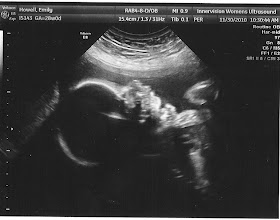

Today was the 28 week appointment for baby Lucy. We had an ultrasound first to check-up on her bowels. They are able to digest more things now(the blood that was causing them to be bright white), and are looking great. So no complications from the bowels! They measured everything else that I'm assuming would be a red flag from the 2 vessel cord. Everything looks good and healthy, but she is measuring about 2 weeks behind. She seems to be tiny like her brother. Part of this ,my Dr. said, is because Landon was a small baby also, so she will probably be smaller, and when you have the cord issue, there are some cases where it does cause the baby to not get all the nutrients it needs to grow fully. She is right at the 21% right now for 28 weeks, and I remember that Landon was around 40% when we had a late ultrasound. And he ended up being 5 pound 10 ounces. So it seems she will be teeny tiny.

We finally got to see her face too! I took a picture of this one with my phone. I'll have to scan it later on because it is a good picture of her. She said that since I'll most likely be back a few more times, she will try to get one again without her hand over her face.